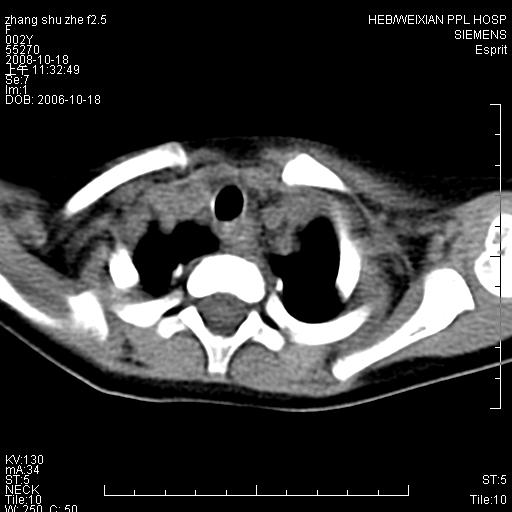

以下是引用dyqct在2009-2-10 21:04:00的发言:[br]年龄?性别?有发烧吗?[br]鼻咽部、口咽部、喉咽部及颈椎前间隙广泛肿厚,明显占位效应并致相应组织变形。ct值22-28hu。[br]考虑:1、颈前脓肿可能性大;[br] 2、建议增强或治疗后复查。

以下是引用jiangjing在2009-2-11 11:37:00的发言:[br]急性病程,鼻咽部、口咽部、喉咽部及颈椎前间隙广泛肿厚,明显占位效应并致相应组织变形.考虑颈部感染性病变(脓肿?);建议行进一步检查。